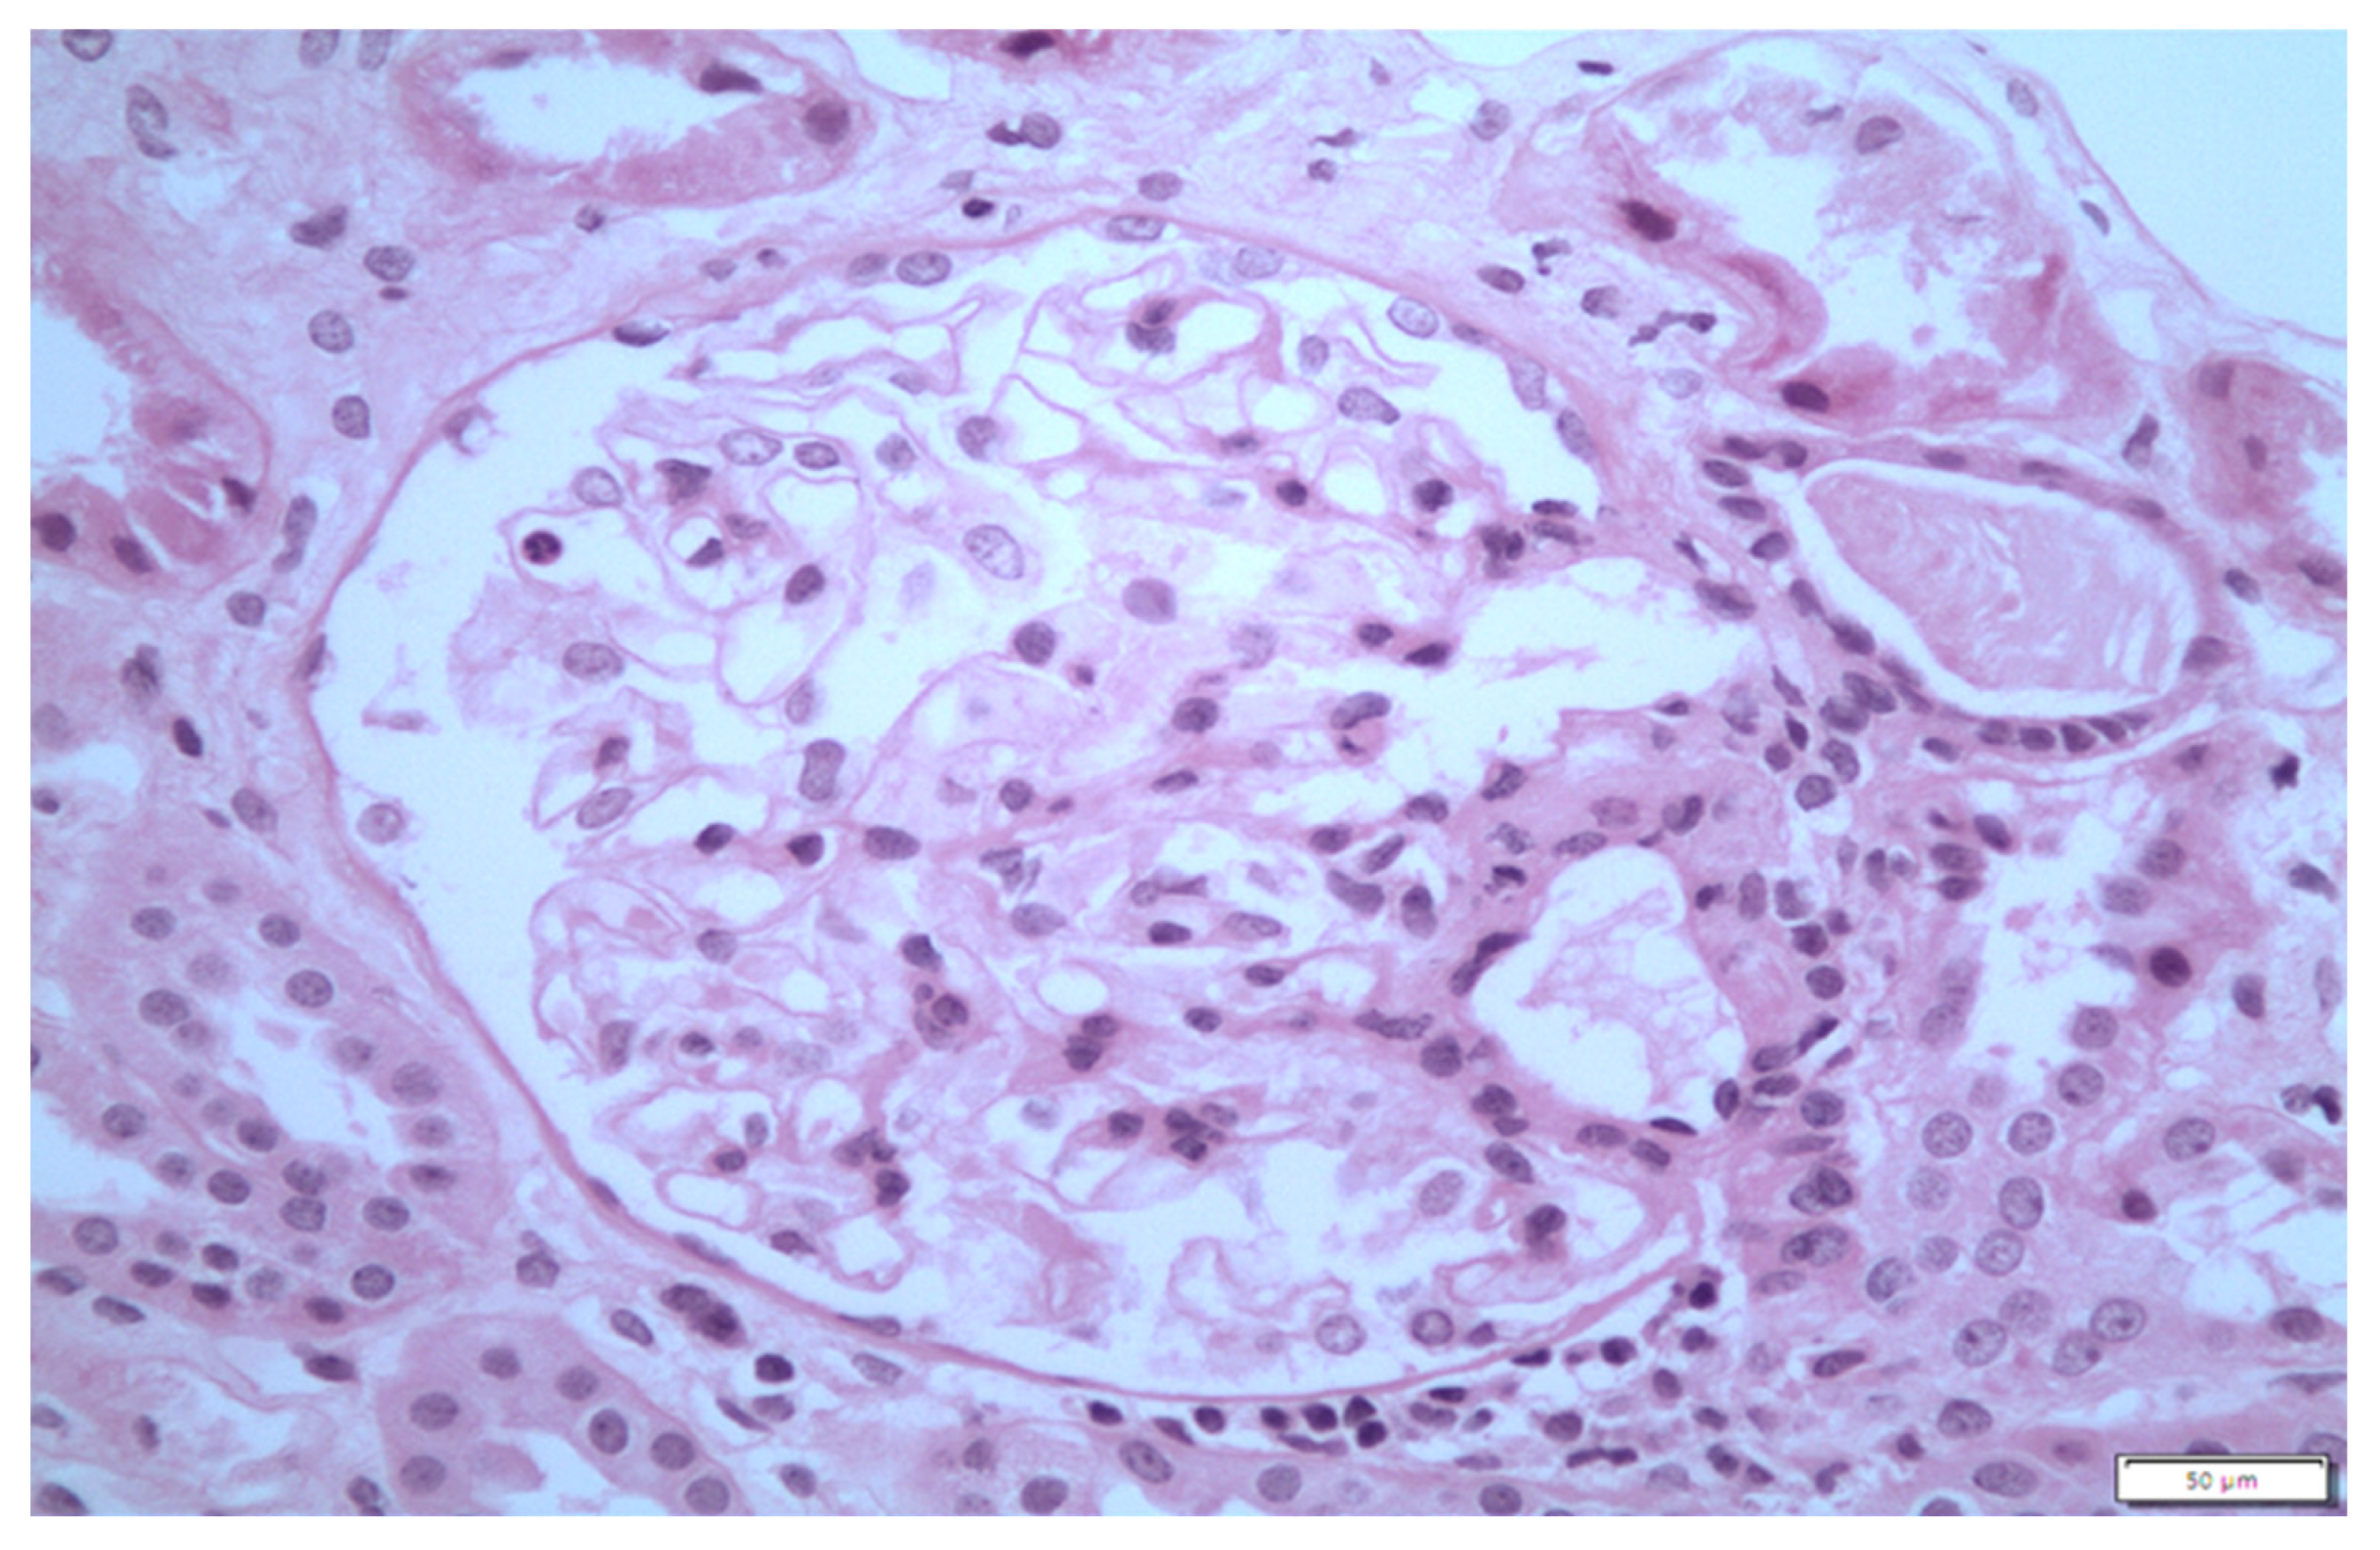

3. Case 2 Description: MCD Associated with D-Penicillamine

4. Case 3 Description: D-Penicillamine-Associated MCD